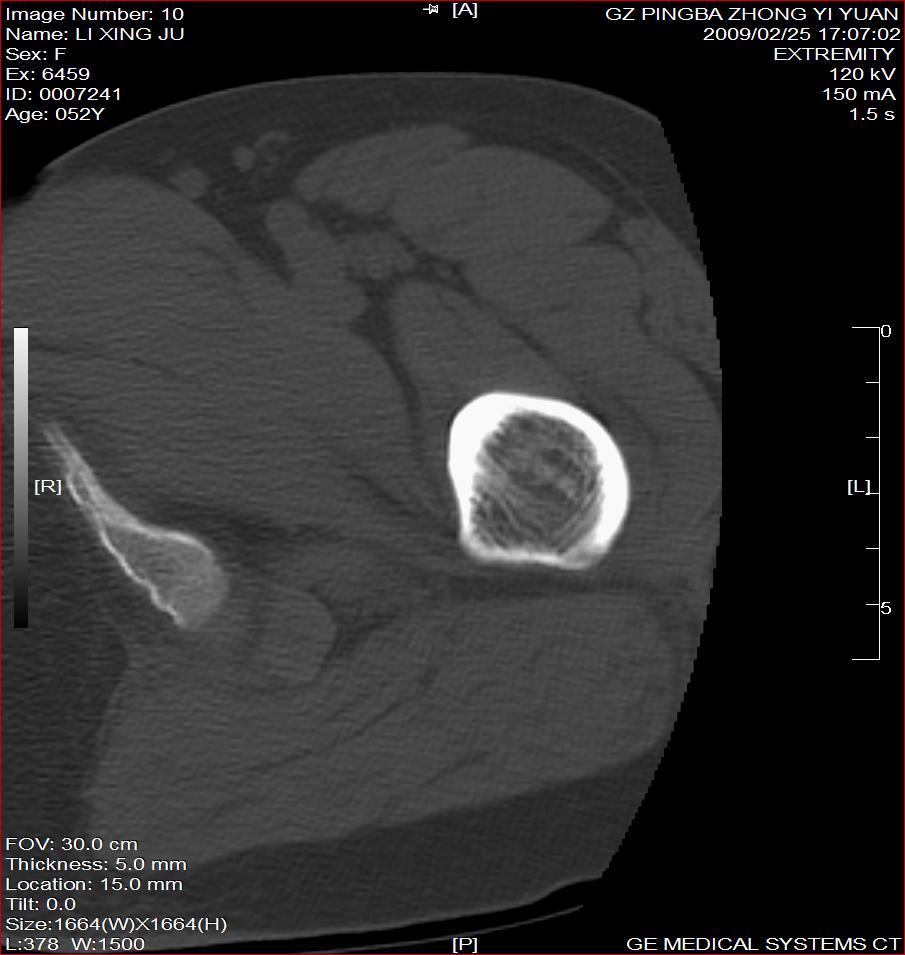

标题: CT18521:左大腿疼痛不适1+月 [打印本页]

标题: CT18521:左大腿疼痛不适1+月

考虑-----股骨骨化性纤维瘤可能性大,不除外---局限性骨纤

考虑:左股骨骨化性纤维瘤

考虑:骨纤或骨梗可能性大

考虑 左股骨骨化性纤维瘤。

骨梗塞

考虑骨化性纤维瘤可能性大